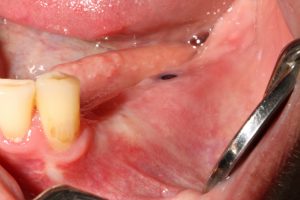

When accessing the area that has to be reconstructed through a subperiosteal tunnel, and performing the whole procedure through the tunnel approach will give us two significant advantages:

1. No incisions are made over the crest, so no suture will be there, reducing to zero the possibility of wound dehiscence

2. As far as no incisions are made over the periosteum that is covering the graft, its osteogenic and revascularization capacity remains intact.

Using a different approach to crestal incision like tunnel approach.

#1. The Tunnel Approach Technique